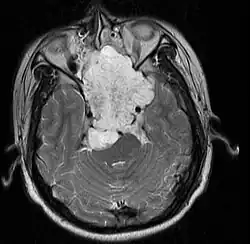

Extenso cordoma de base de crânio (massa branca na imagem) em paciente homem de 17 anos em imagem produzida por ressonância magnética.

Cordomas são tumores malignos de crescimento lento, que se formam como remanescentes da notocorda. Um terço se forma na base do crânio, podendo também se formar na região lombossacral.[1][2] Histologicamente, são benignos, mas apresentam comportamento maligno por serem invasivos e por sua capacidade de metástase.